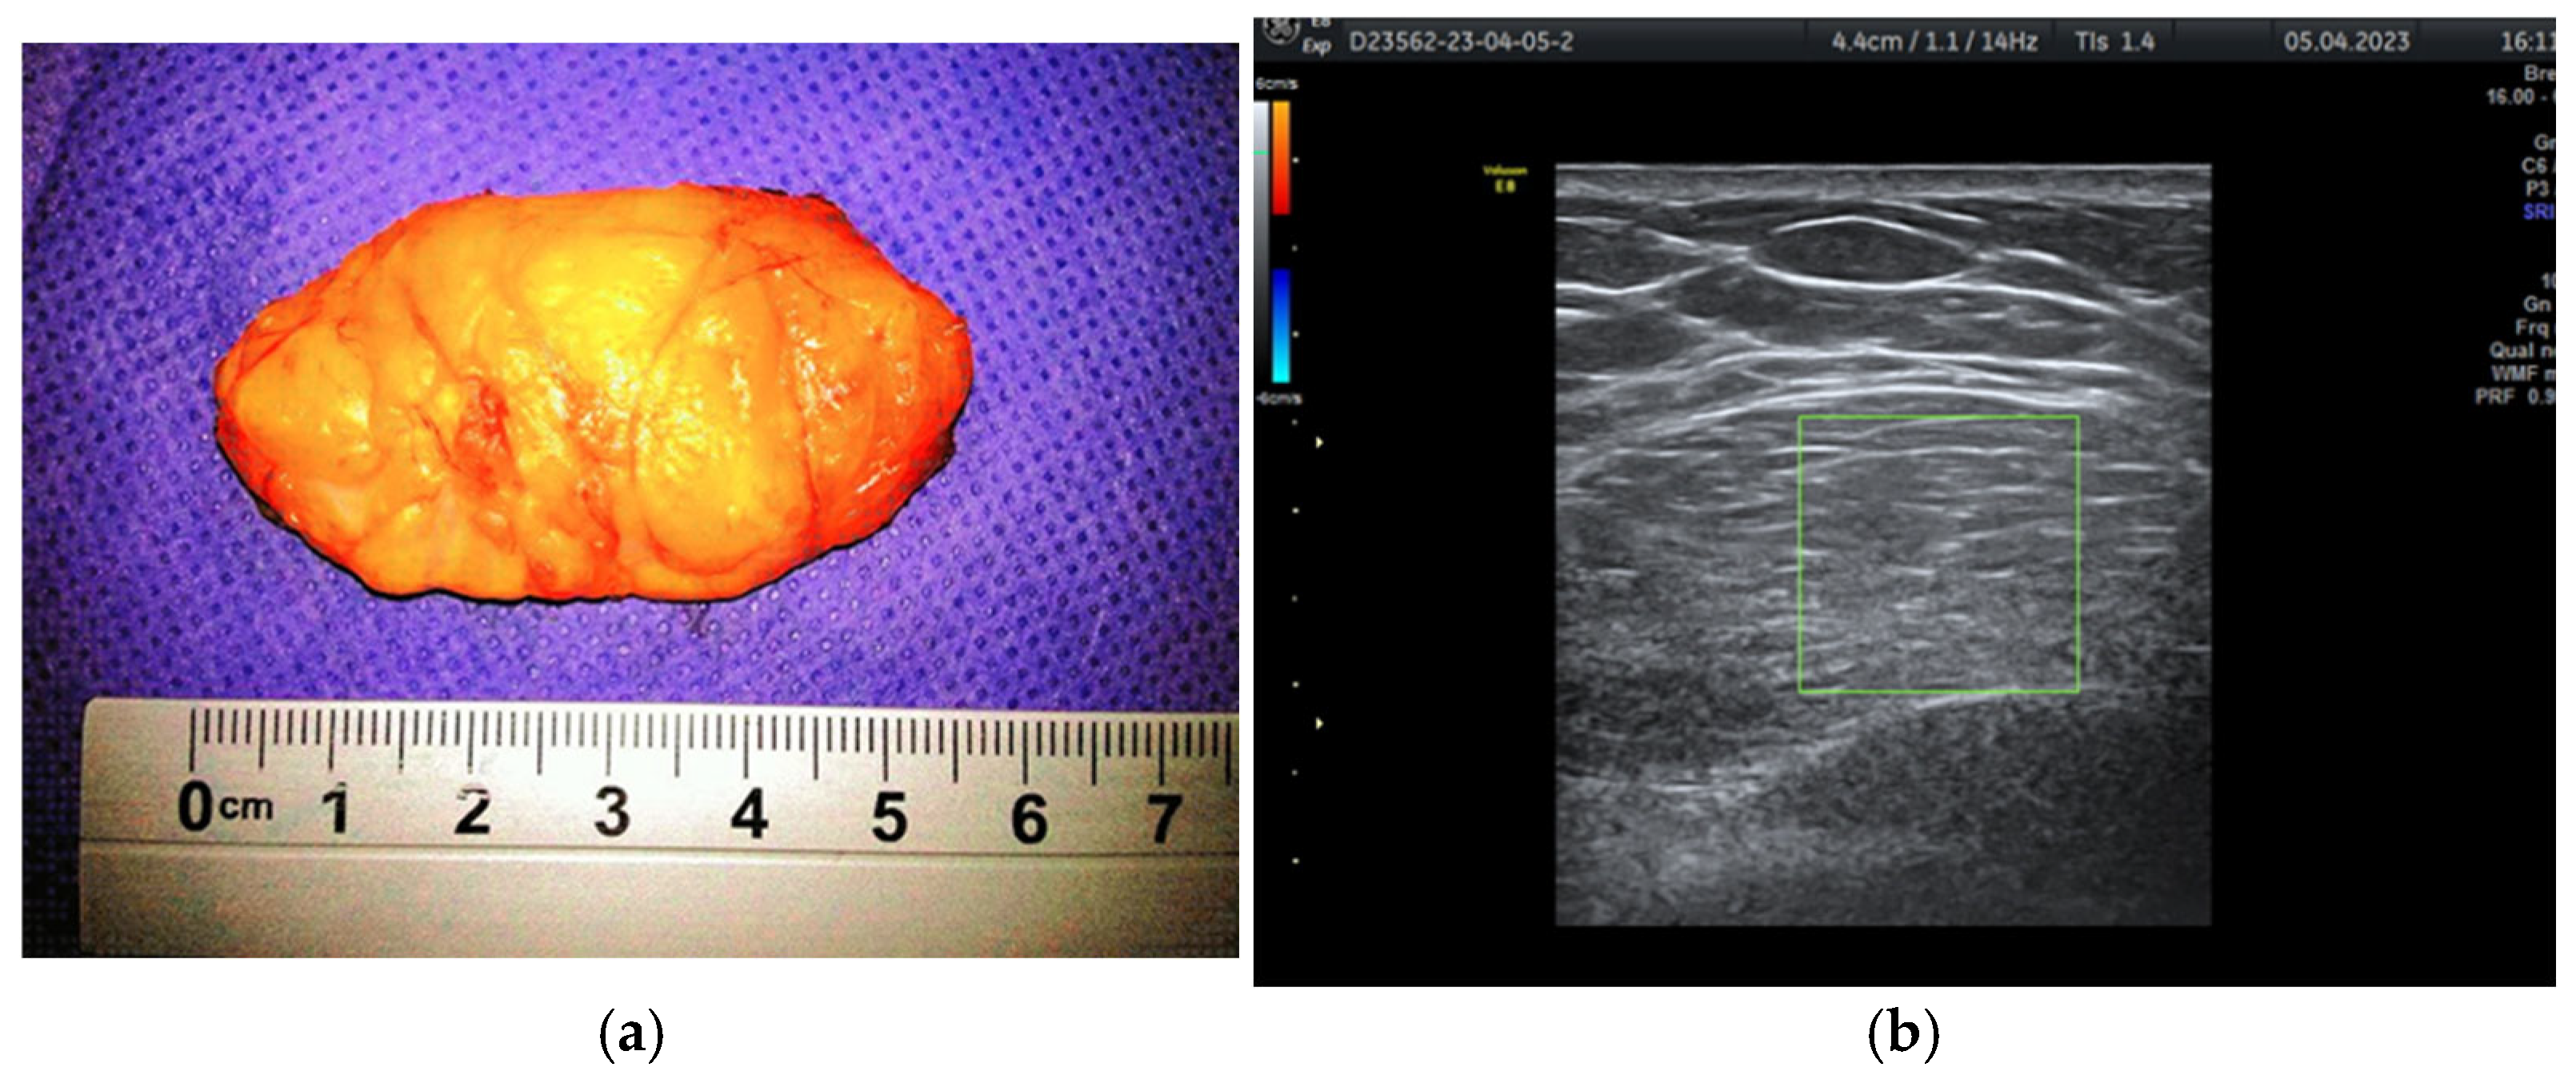

Surgical treatment for cases of breast hamartoma involved lumpectomy with a margin of normal tissue surrounding the tumor (Figure 5) to minimize the risk of recurrence. In all cases, frozen section analysis was performed.

Figure 5.

Hamartoma excised with surrounding normal breast tissue, marked for frozen section.

Regarding the macroscopic appearance of the tumors, their sizes ranged from 1 cm to 17 cm, with an average of 6.75 cm. Hamartomas in adolescent girls can grow to considerable sizes (>10 cm) and may resemble a giant juvenile fibroadenoma. For instance, a single case of a 16-year-old with a 5 cm tumor was diagnosed.

Typically, the tumor is enclosed in fibrous tissue that delineates it from the surrounding breast tissue. Upon sectioning, the hamartoma presents as a fleshy mass with a rubber-like consistency and exhibits yellow or gray coloration (Figure 6a,b).